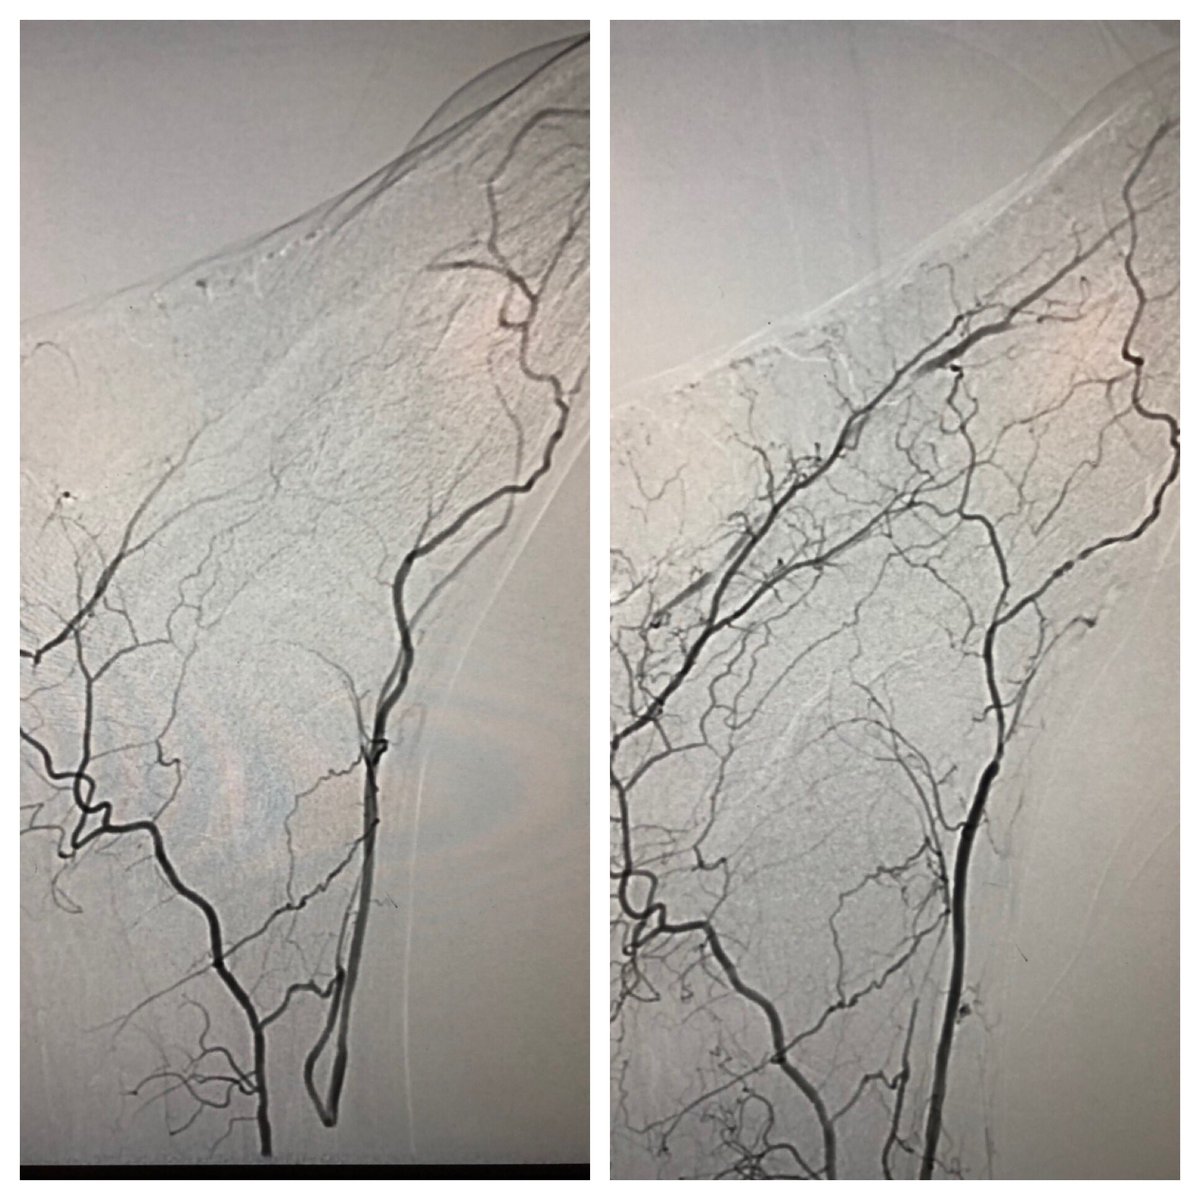

Great case last week to close out enrollment in FAST II evaluating the Freedom Flow orbital atherectomy device (currently limited to investigational use, not in commercial distribution). Excellent result with OA and PTA alone. Look forward to the trial results! #SCAIPAD @TCAVIRF